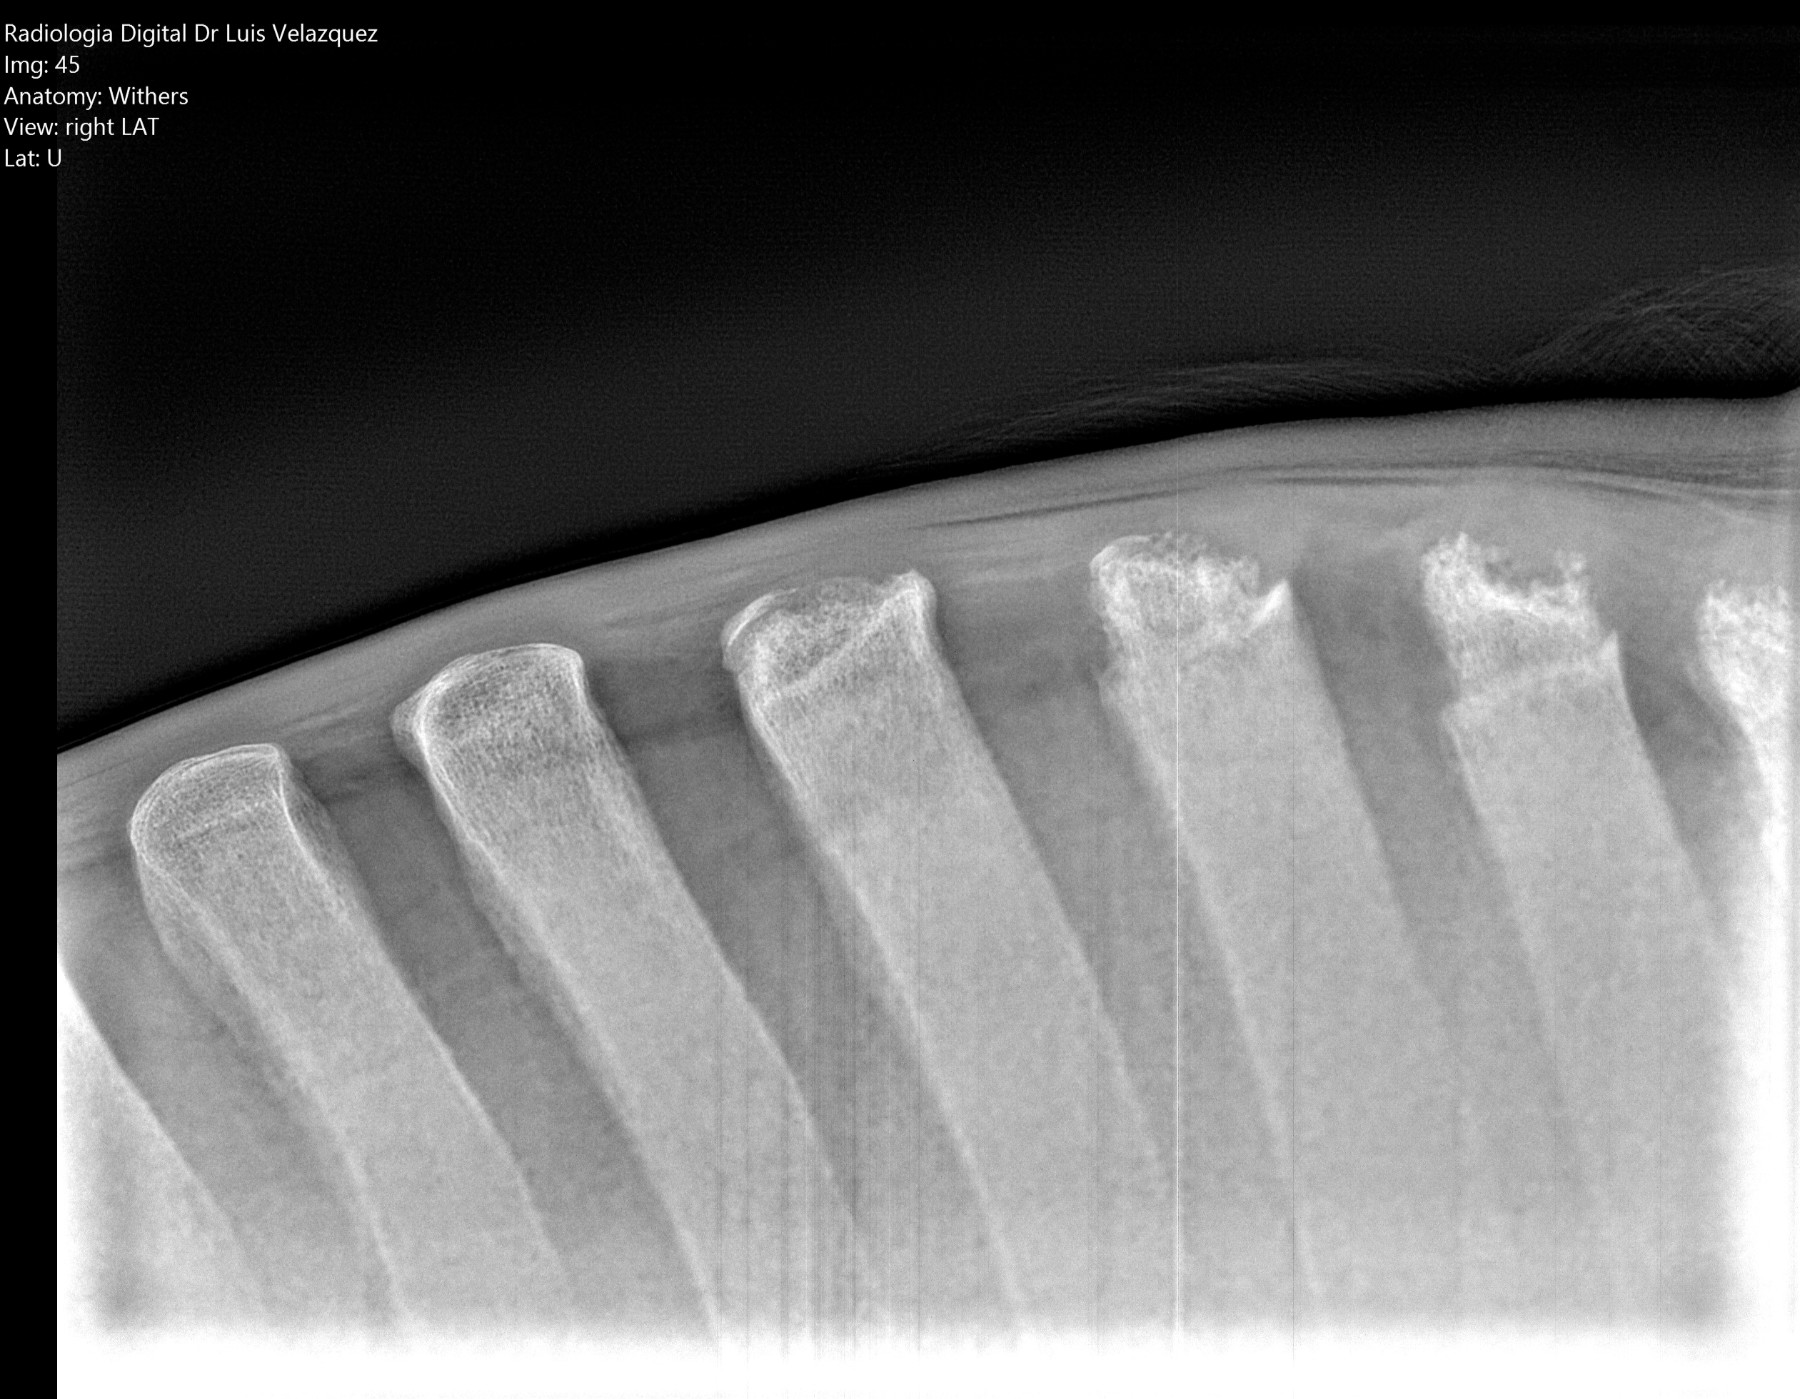

Radiología Digital como Herramienta Complementaria en el Dictamen de Bienes Muebles